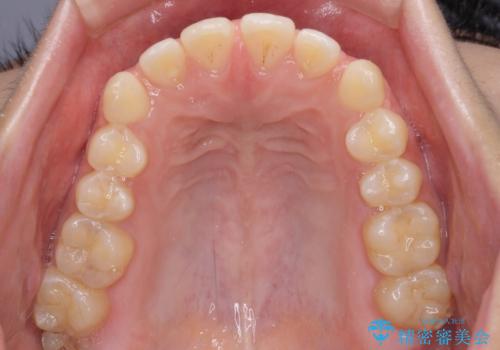

- 上下前歯の隙間と咬み合わない前歯を気にして来院された患者様です。

開咬の治療は、前歯を閉じるように動かすとともに、上下臼歯を圧下(骨内にめり込ませる)させることで進めて行きます。

インビザラインは臼歯の圧下を効果的に行えるため、インビザラインを用いて矯正治療を行うこととしました。

開咬とすきっ歯は、舌の突出癖改善が必須となるため、トレーニングを徹底的に行うよう指示しました。